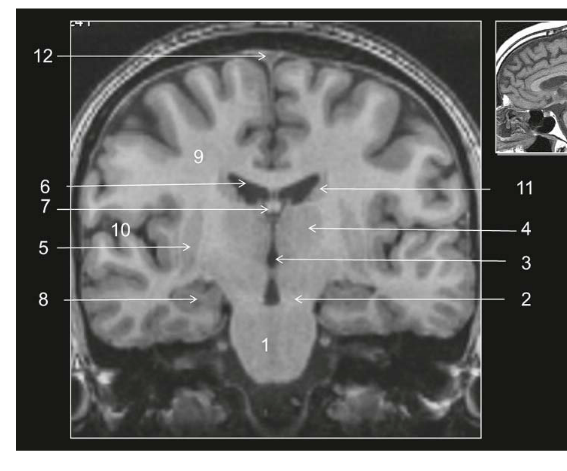

Coupe ?

Légende ?

Coupe ? Légende ?